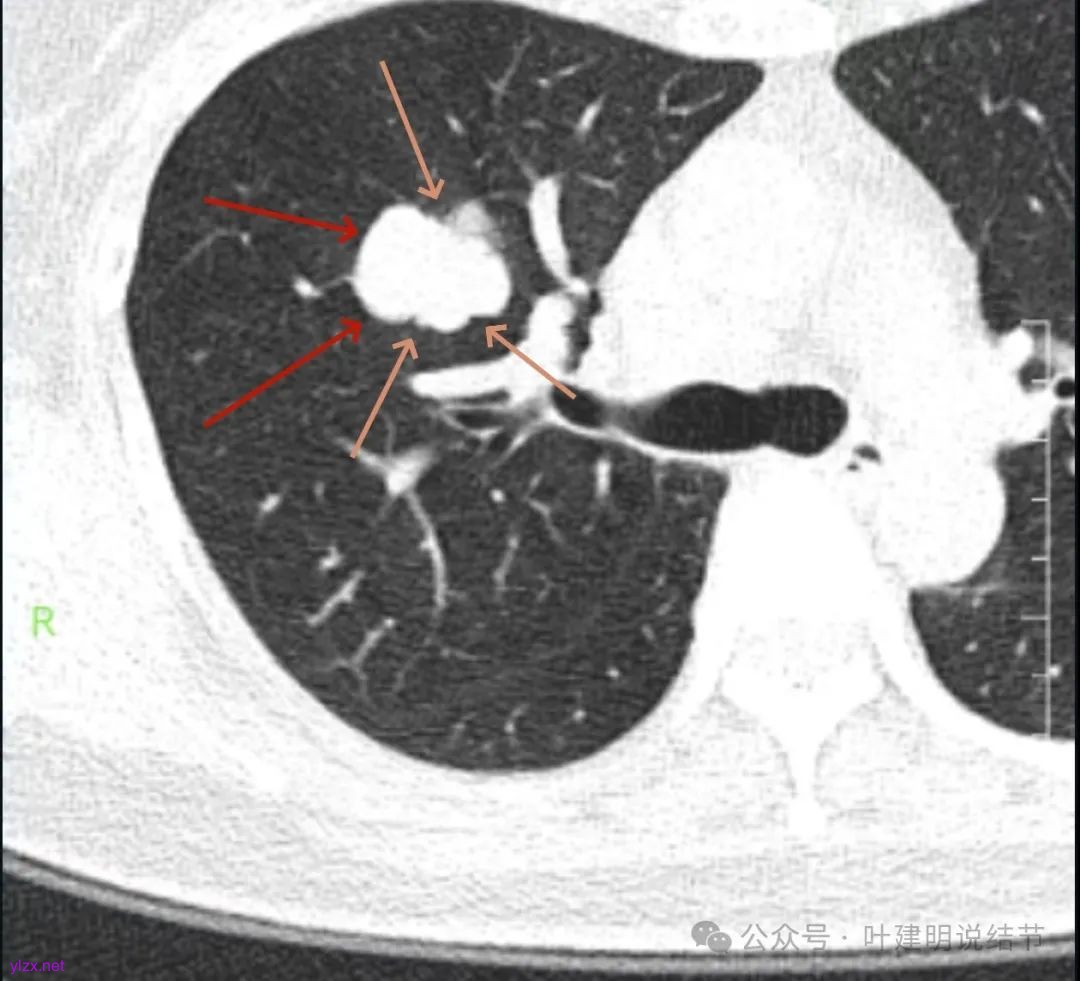

咳嗽近三周,CT检查提示右肺上叶空洞病变。

影像展示与分析:

腔静脉旁明显肿大淋巴结。

你的右上叶这个病灶基本上肯定是肺癌,要尽快处理。从影像上看有以下特点:1、整体轮廓清楚,不似普通炎症的周围有晕或阻塞性改变;2、边缘明显的浅分叶,总体上的感觉膨胀性明显,不管哪个层面看上去都是鼓鼓的;3、边缘区域有磨玻璃成分而且也是分叶状的;4、部分层面见血管进入;5、空腔病灶的壁厚薄不均,内壁不光滑。我考虑中低分化肺癌,由于腔静脉旁有明显肿大淋巴结,需要进一步完善增强CT以及PET-CT检查以明确有无远处转移,是否仍可手术治疗(从病灶本身来说是可以肺叶切除治疗的)。要尽快处理。意见供参考!